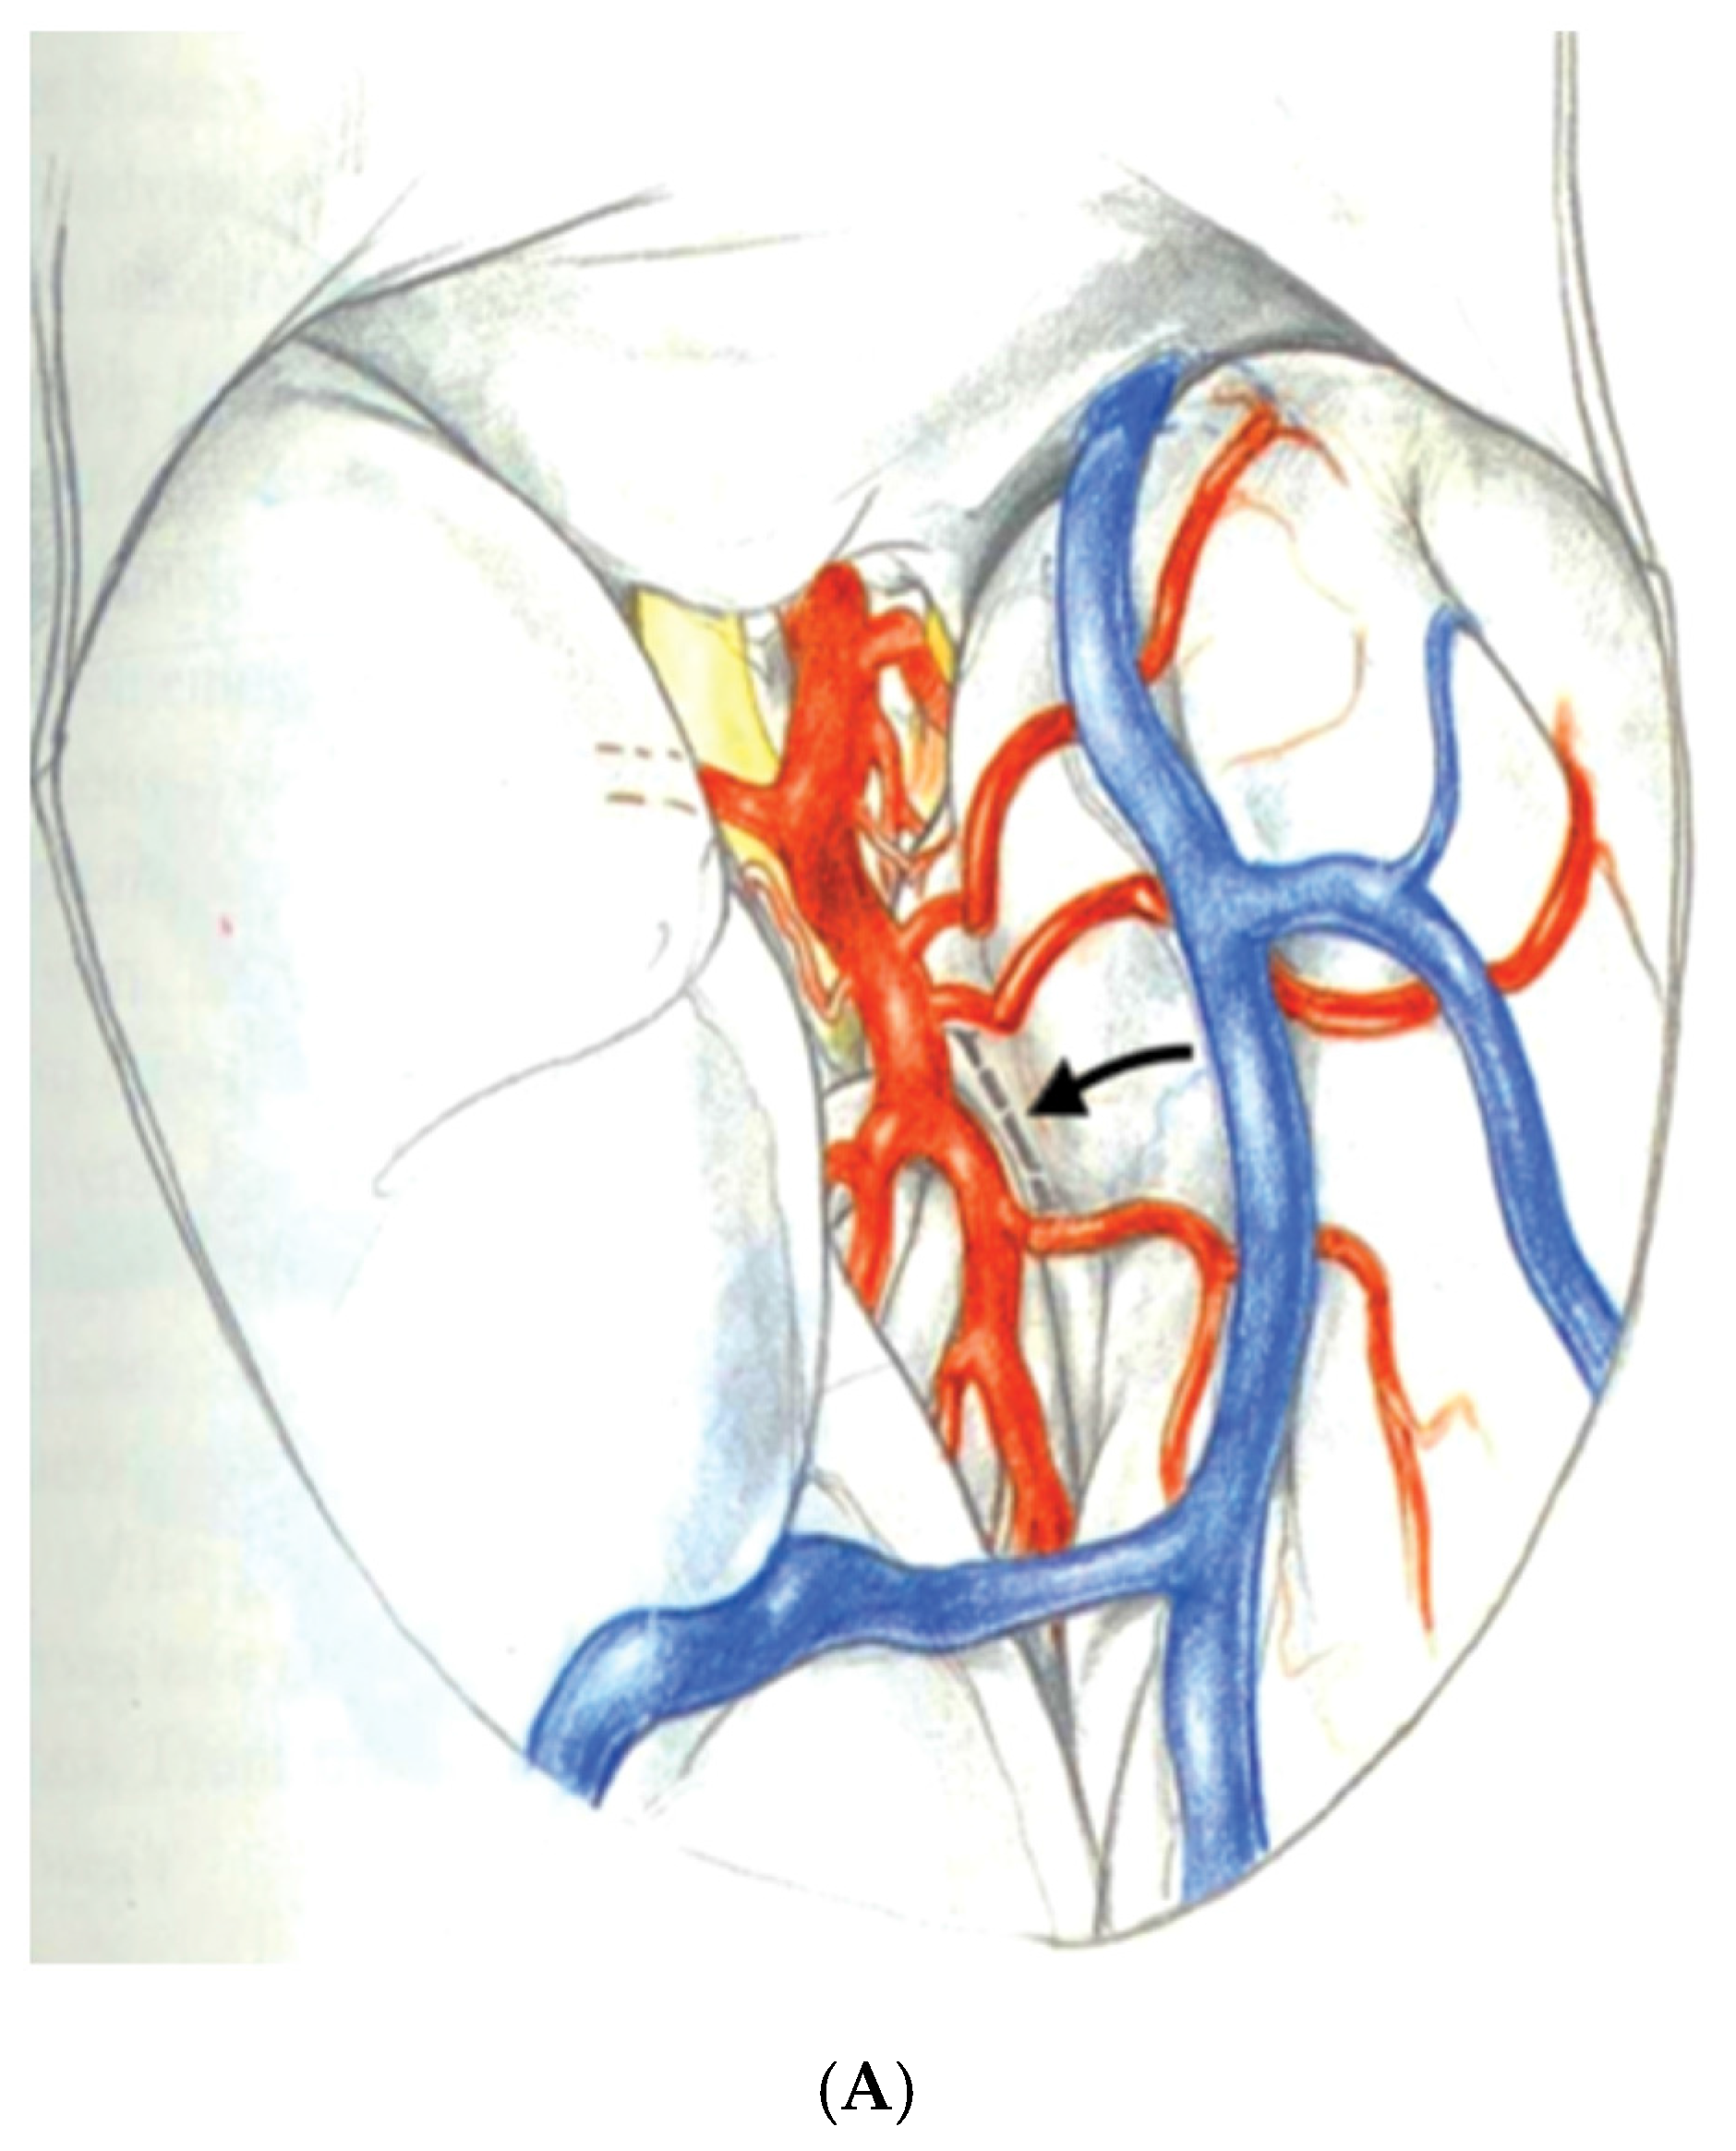

Yasargil, et al. generated considerable interest in SAH for MTLE after the description of a selective surgical approach using the trans-Sylvian fissure route to remove the mesial temporal structures [53]. In the technique described by Yasargil, the Sylvian fissure is opened to expose the inferior aspect of the circular sulcus of the insula. An incision in the circular sulcus between middle cerebral temporal opercular arteries and dissection through the white matter of the temporal stem will open the temporal ventricular horn providing sufficient exposure to identify then remove the hippocampal formation and amygdala. Figure 3A,B An advantage of this surgical approach to SAH is to minimize white matter dissection required to access the mesial temporal structures as compared with Niemeyer’s technique. The disadvantages of the trans-Sylvian approach are mostly related to the demanding technical requirements of widely opening the Sylvian fissure and working between the middle cerebral vessels within the fissure. Manipulation of the middle cerebral arteries during surgery in addition to the extra-pial resection of the hippocampus are technique related aspects of the procedure that may increase the risk of vascular injury [54].

Figure 3. Reprinted and Modified by permission from Springer Nature: Adv Tech Stand Neurosurg, Yaşargil MG, Teddy PJ, Roth P. Selective amygdalohippocampectomy: operative anatomy and surgical technique. Copyright, 1985 [55]. (A) The Sylvian fissure is opened widely to expose the inferior delineation of the insula called the circular sulcus with the planned white matter incision marked in a dashed line between two middle cerebral opercular temporal arteries; (B) Surgeon’s view into the opened ventricle illustrating the choroid plexus (C), hippocampus (H), collateral eminence (star), middle cerebral vessels (M1 and M2), and amygdala (A). Numbers represent steps in the extra-pial removal of mesial temporal structures: coagulation and division of the hippocampal vessels (steps 1 and 2), disconnection of the hippocampal body from the hippocampal tail (step 3), opening the collateral eminence to empty and remove the parahippocampus (steps 4 and 5), and remove uncus and amygdala (step 6).